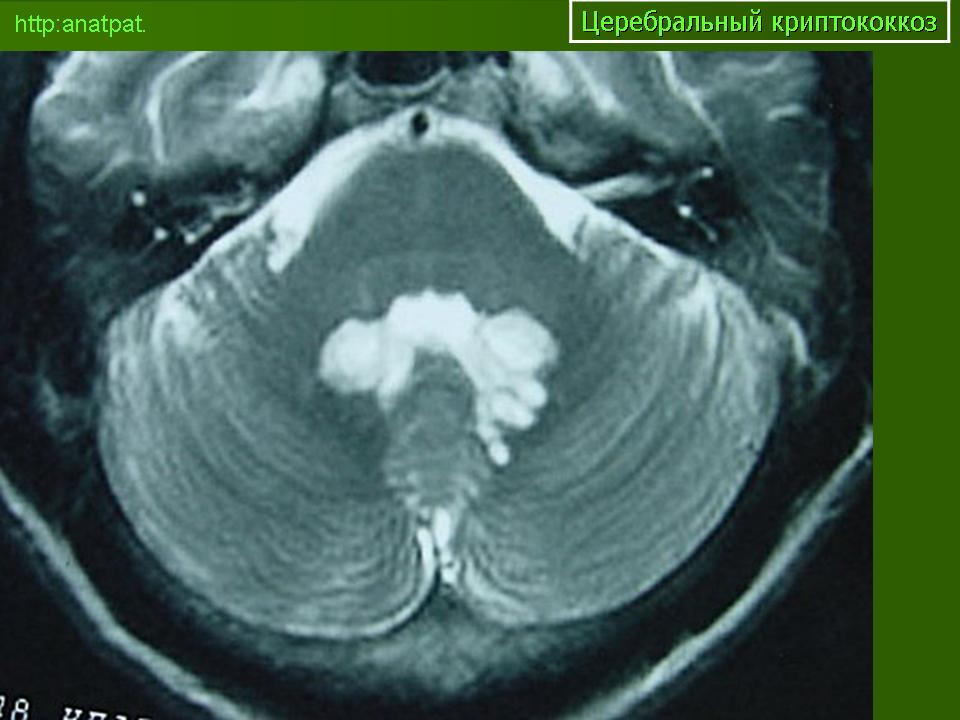

Отдел патологии ТСМ-UNICAMP

Церебральный криптококкоз у ВИЧ инфицированного

Приложения:

150920-9.jpg150920-11.jpg150920-15.jpg150920-21.jpg150920-23.jpg150920-27.jpg150920-33.jpg150920-46.jpg150920-61.jpg150920-79.jpg150920-81.jpg